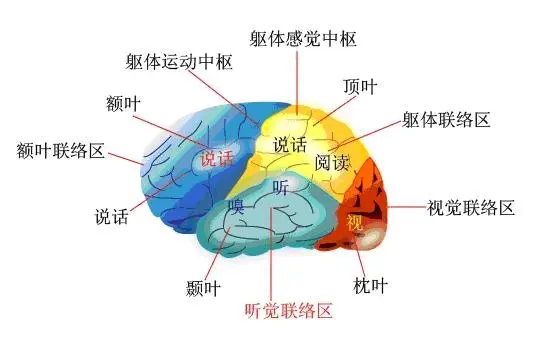

3.3 大脑

中枢神经系统的高级部位,由左、右两个大脑半球组成,两半球间有横行的神经纤维相联系。

每个半球包括:大脑皮层(大脑皮质):是表面的一层灰质(神经细胞的细胞体集中部分)。

人的大脑表面有很多往下凹的沟(裂),沟(裂)之间有隆起的回,因而大大增加了大脑皮层的面积。

人的大脑皮层最为发达,是思维的器官,主导机体内一切活动过程,并调节机体与周围环境的平衡,所以大脑皮层是高级神经活动的物质基础。

(1)驱动的运动功能

大脑的运动系统负责产生和控制运动。产生的运动从大脑通过神经传递到身体运动神经元,达到控制肌肉的作用。皮质脊髓束将运动信息从大脑,脊髓传递至到躯干和四肢。脑神将运动信息传递至眼睛,嘴巴和脸部区域。

(2)感官的感觉功能

感觉神经系统涉及感觉信息的接收和处理。

这些信息通过特定的感受器官(视觉,嗅觉,听觉和味觉)的被接受传至大脑。

- 视觉皮质:视觉首先由视网膜接外部光刺激,其被视锥细胞和视杆细胞接受并转化为神经信号,并最终发送到枕叶中的视觉皮质。

- 听觉皮层:听觉和平衡觉都是在内耳中产生的。平衡觉是由内耳内的液体运动产生的而由小骨骨骼产生的传播振动产则负责传递声音信息。他们通过前庭耳蜗神经产生神经信号。神经信号通过耳蜗核,上极的橄榄核,内侧膝状核,最后到听觉皮层。

- 嗅觉皮质:嗅觉由鼻腔中嗅粘膜上皮中的受体细胞产生。该信息通过颅骨的相对可渗透的部分到嗅神经。这种神经把信息传递到嗅觉皮层。值得一提的是,在所有感觉信息中,只有嗅觉信息不需要经过丘脑上的核团而直接传递至到大脑皮层。

- 味觉皮层:味觉是由舌头上的受体产生的,并沿着面部和咽喉神经传入脑干。一些口腔中的感信息也通过迷走神经从咽部传入这一区域。然后将信息从这里通过丘脑传递到味觉的皮层

- 其他感觉:大脑从皮肤接收关于触摸,压力,疼痛,振动和温度的信息。

(3)情绪情感

尝试将某些大脑区域的喜怒哀乐等基本情绪相关联目前还存在着极大的有争议,一些研究没有发现与情绪相对应的特定位置。

杏仁核、眶额叶皮质、脑岛及外侧前额叶皮层区域似乎参与到了情绪的加工过程。

(4)语言思维

虽然传统上语言功能被认为是定位于威尔尼克区(Wernicke)和布洛卡区(Broca),但现在人们普遍认为,更广泛的皮层区域对语言使用有贡献。

语言如何被大脑表征,处理和获取的是心理学和神经科学研究等领域正着力研究的一个问题。

这也是人工智能深度学习目前研究最热门的领域。

(5)执行功能

执行功能是允许认知控制行为所需的一套认知过程的总称:他负责选择并成功监测促进实现所选目标的行为。

执行功能通过注意控制和认知抑制过滤无用信息和降低与抑制无关的刺激,处理和操纵在工作记忆中保存的信息,同时思考多个概念的能力,并以认知灵活性切换任务,抑制冲动性行为等。